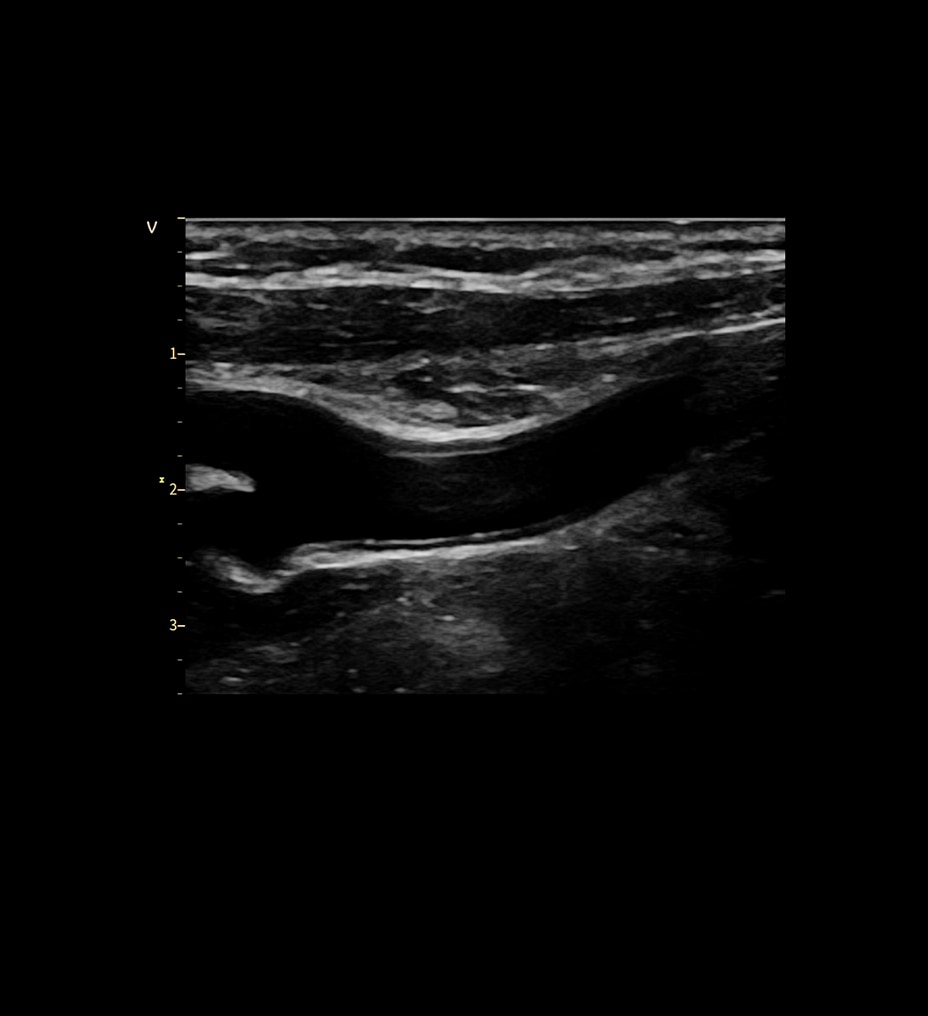

Revolution Ascend'i kullanıma sunarak, birinci sınıf BT sistemimizle aynı kullanıcı arayüzünü (UI) dahil ediyor ve işlevleri standartlaştırmaya başlıyoruz. Kullanıcı Arayüzü, akıllı anatomi tanıma ve lokalizör ayarları için Smart Plan gibi özelliklerle günlük ihtiyaçlarınız düşünülerek tasarlanmış yeni Clarity Operatör Ortamına sahiptir. Ek olarak Auto Prescription, uzmanlık düzeyinizden bağımsız şekilde hastaya özel tarama parametreleri önererek tarama kurulumunu ayarlar ve tüm taramalarda istenen görüntü kalitesi ve doz performansını sağlar.

Kaliteden ödün vermeden kapsamlı ayrıntı, üstün kontrast, doku ve görüntü netliği sağlar.